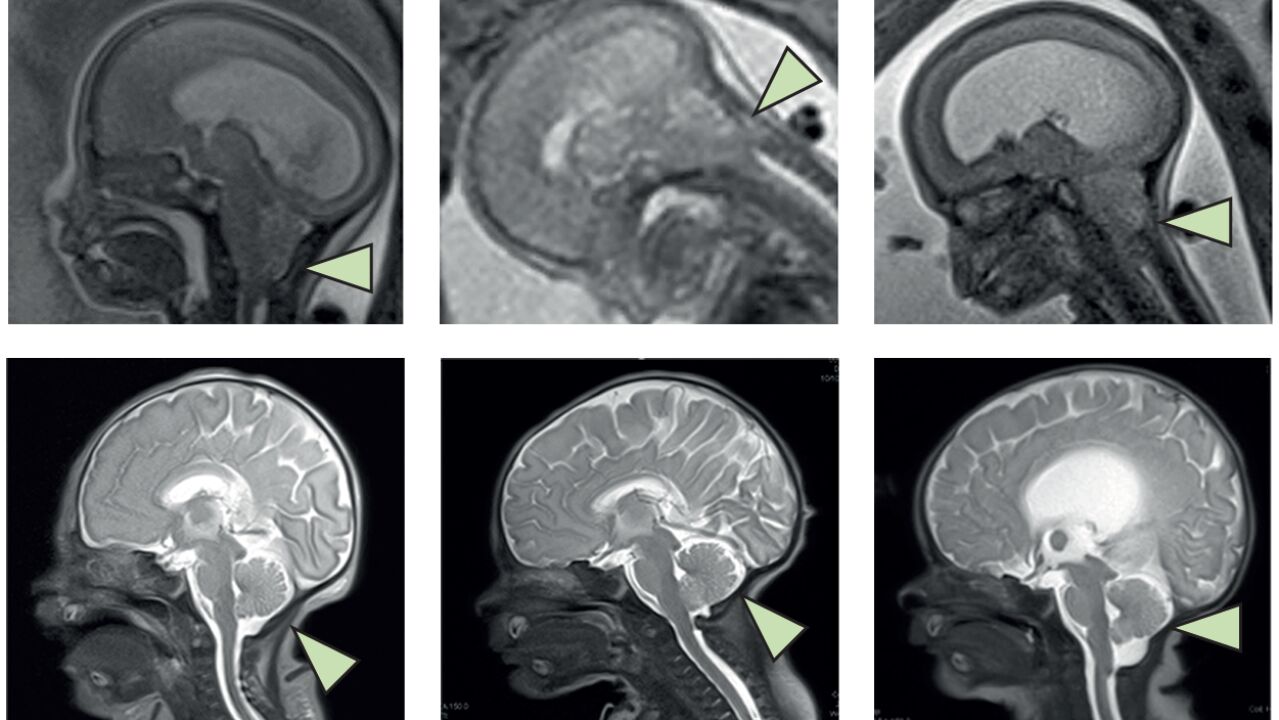

Un estudio publicado en The Lancet confirma en humanos la seguridad de las células madre para tratar la espina bífida...